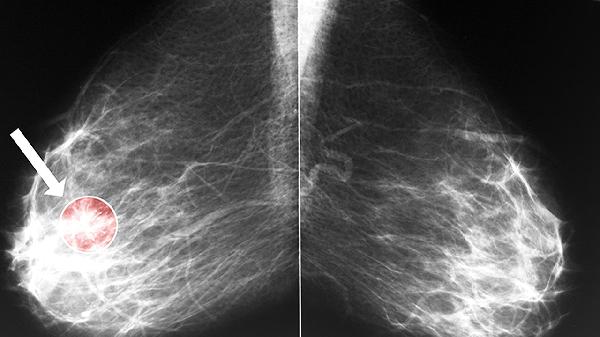

由于腫瘤細胞增殖活性低,高分化腺癌體積增長通常需要較長時間,臨床癥狀出現(xiàn)較晚。影像學檢查可能顯示邊界相對清晰的腫塊,增強掃描時強化程度多呈漸進性。部分病例甚至可保持穩(wěn)定狀態(tài)數(shù)年,但需警惕后期去分化可能。